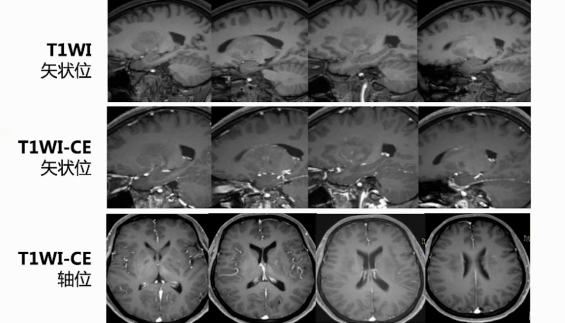

颅脑磁共振:双侧基底节区、放射冠区域片状长T2高信号,累积部位深,无显著占位效应,呈长T1长T2信号。增强后,仅见小斑片状轻度强化影,左侧基底节区及放射冠区域较明显,脑岛区无明显异常强化。DWI信号增高,部分区域ADC信号减低,提示弥散受限。多体素MR波谱扫描多数区域胆碱峰升高,部分体素N - 乙酰天门冬氨酸峰降低。SWI和颅脑MRA扫描未见明显微出血及血管异常。颅脑灌注加权成像显示病灶区域脑血流量CBF、脑血容量CBV轻度升高,达峰时间TTP及平均通过时间MTT稍延迟。